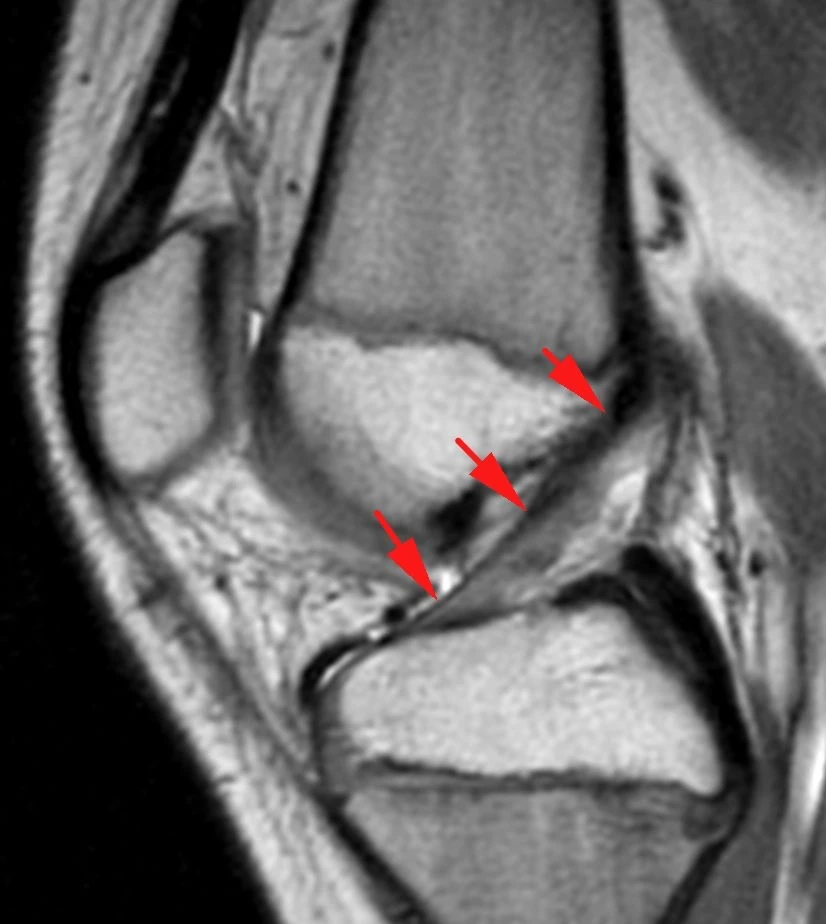

Обширная, ветвистая венозная мальформация (ранее известная, да и до сих пор тоже, как гемангиома) мягких тканей области коленного сустава.

Картина типичная, дифференциальная диагностика не требуется.

Представляет собой скопление аномальных, расширенных, извитых венозных сосудов, стенка которых гистологически не отличается от стенок обычных вен. Хорошо видны связи мальформации с обычными венами. Внутри некоторых из полостей видны выпадение сигнала, которые являются флеболитами (кальцинированными внутрисосудистыми тромбами).

Кстати, может никак не проявляться клинически, будучи даже таких больших размеров.